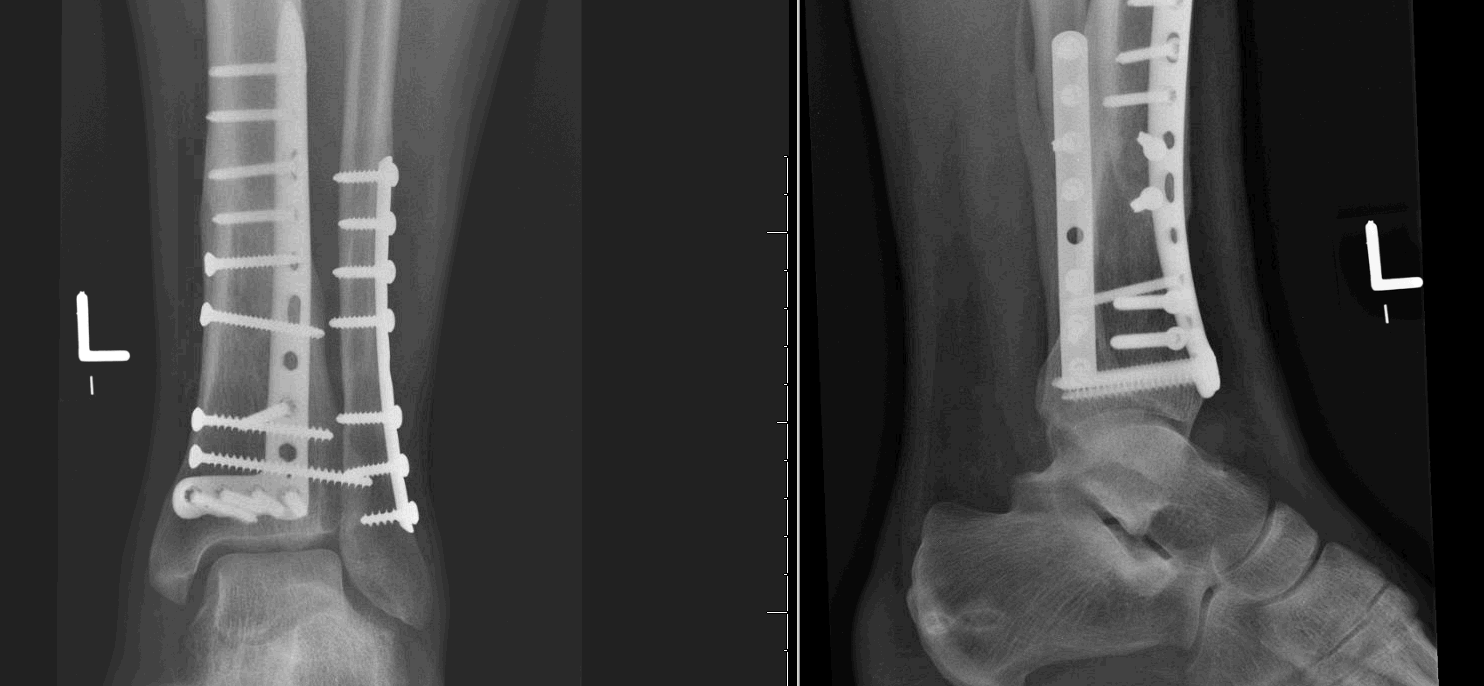

ORIF of Tibia and Fibular Fractures with Drain in Place and Soft Tissue Cpt Code For Orif Distal Tibia And Fibula Fracture the current procedural terminology (cpt ®) code 27759 as maintained by american medical association, is a medical. Did orif on seriously comminuted tib fx and orif of distal fibula. if you fracture your tibia or fibula, you might need orif to bring your bones back into place and help them heal. You might need this procedure to treat. Cpt Code For Orif Distal Tibia And Fibula Fracture.

Tibia and Fibular Fractures with Open Reduction Internal Fixation (ORIF Cpt Code For Orif Distal Tibia And Fibula Fracture if you fracture your tibia or fibula, you might need orif to bring your bones back into place and help them heal. In c1 fractures, there is fracture of the fibula above the level of the syndesmosis. Did orif on seriously comminuted tib fx and orif of distal fibula. open reduction and internal fixation (orif) is a type. Cpt Code For Orif Distal Tibia And Fibula Fracture.

Tibia and Fibular Fractures with Open Reduction Internal Fixation (ORIF Cpt Code For Orif Distal Tibia And Fibula Fracture You might need this procedure to treat your broken. He wants to charge 2 seperate codes due. Did orif on seriously comminuted tib fx and orif of distal fibula. in this procedure, the provider treats a distal fracture of the fibula, or a break in the end of the fibula bone of the leg, including. open reduction and. Cpt Code For Orif Distal Tibia And Fibula Fracture.